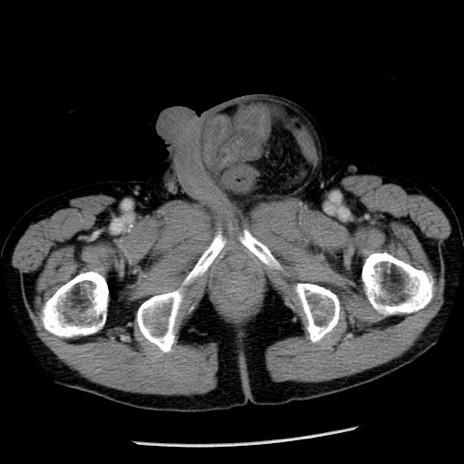

症例26(横断像)

冠状断像

【症例】80歳代男性

【主訴】嘔吐

【現病歴】昨晩2回嘔吐あり、今朝になっても嘔吐あり。来院。

【既往歴】胃潰瘍

【身体所見】意識清明、BT 37.6℃、BP 166/95mmHg、HR 100bpm、SpO2 97%、腹部:平坦・軟、腸蠕動音聴取良好、圧痛なし。

【データ】WBC 21900、CRP 1.46